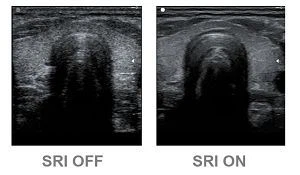

The SRI technology markedly diminishes undesired speckle, tissue echoes for confident clinical diagnosis.